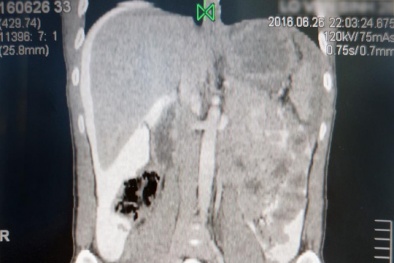

Cảnh giác trước những biến chứng nguy hiểm của sỏi thận

Những dấu hiệu thầm lặng cảnh báo sỏi thận